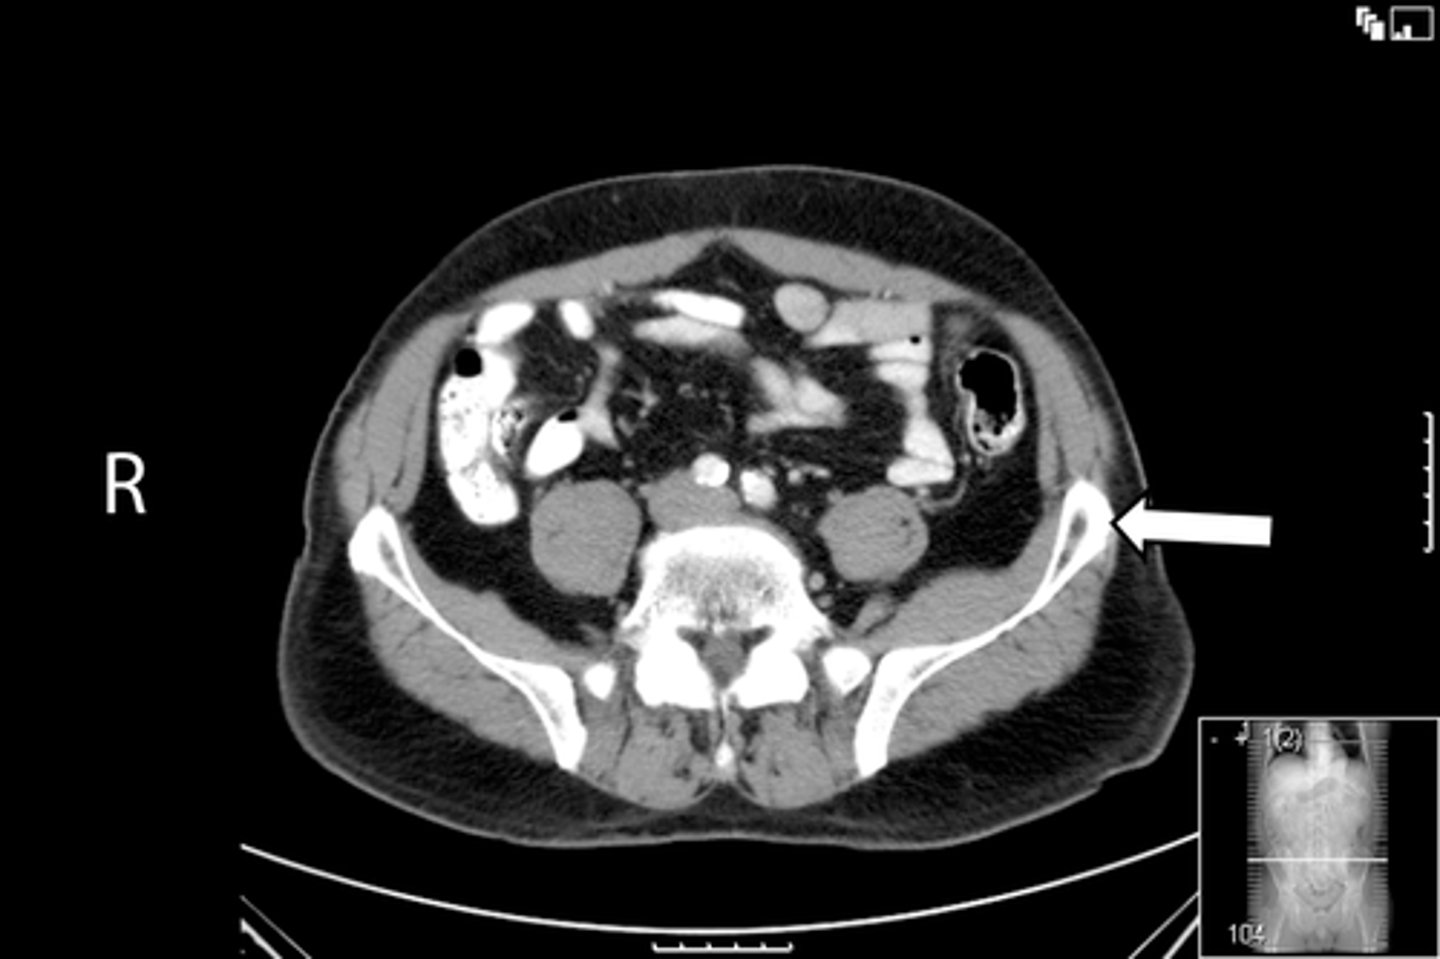

Axial bony pelvis CT

What is the image?

32

L ilium

<p>What is indicated in the image?</p>

New cards

What is indicated in the image?

34

R ilium

36

Sacrum